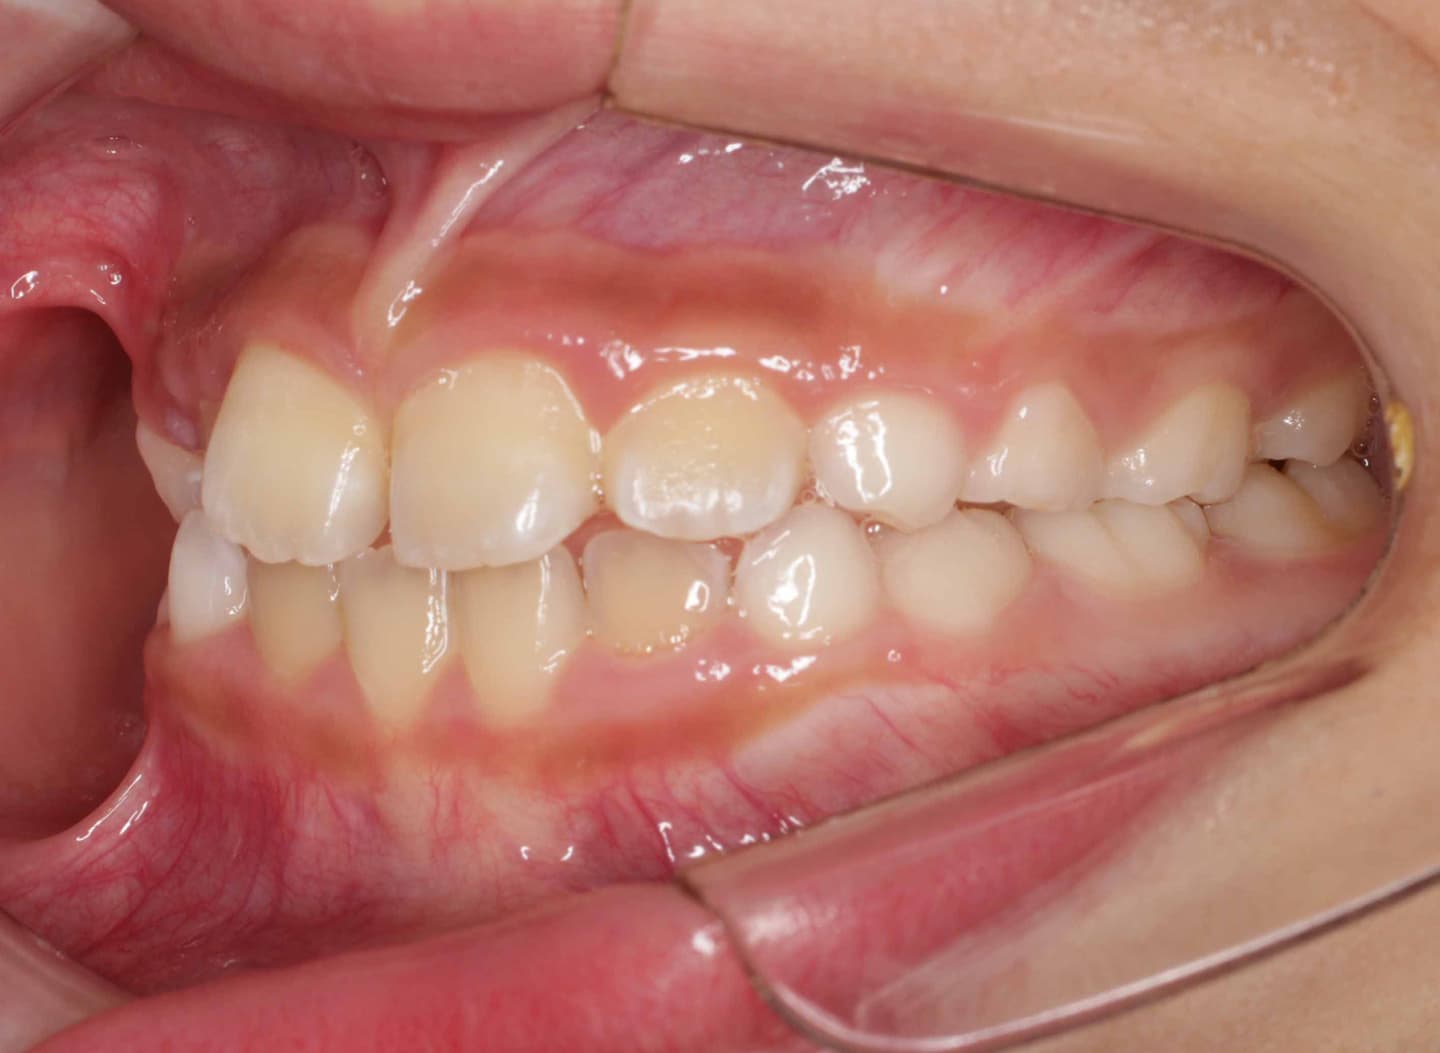

治療後(12ヶ月後)